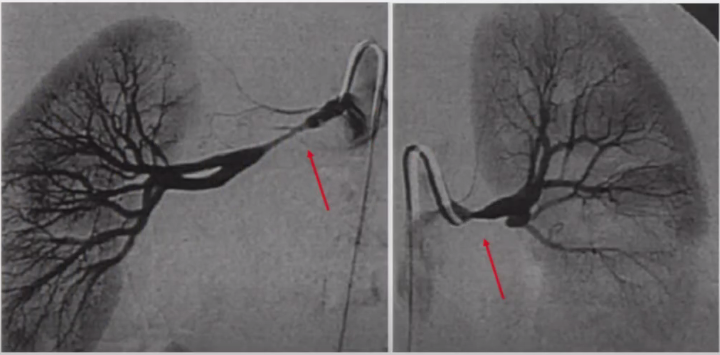

2. 鉴别诊断

➤ 动脉粥样硬化性狭窄或斑块

FMD的狭窄常发生在动脉的中-远段,PTA可以很好地解除狭窄(图12);而动脉粥样硬化性狭窄常发生在动脉分叉起始段,PTA常遗留残余狭窄(图13)。

图12

图13